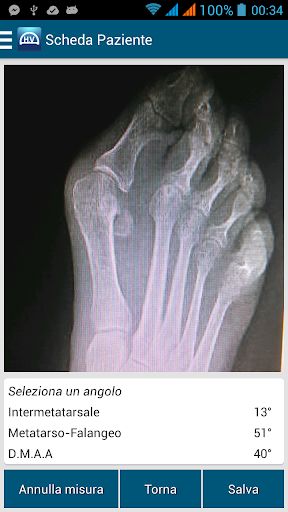

Hallux Valgus, infatti, permette di misurare, in maniera del tutto affidabile e ripetibile, le deformità angolari di pazienti affetti da deformità angolari dell’ avampiede a partire dall’ inserimento di immagini fotografiche e radiografiche a partire dalle quali si effettuano le misurazioni angolari della deformità prima e dopo la correzione chirurgica, fornendo all’ operatore, in maniera immediata, i dati sensibili del paziente.

Hallux Valgus è in grado di calcolare, in tempo reale, la variazione (in gradi) degli angoli di interesse tra i valori ottenuti su immagini pre correzione chirurgica e quelli ottenuti su immagini post correzione chirurgica, fornendo quindi un trend di correzione chirurgica angolare.